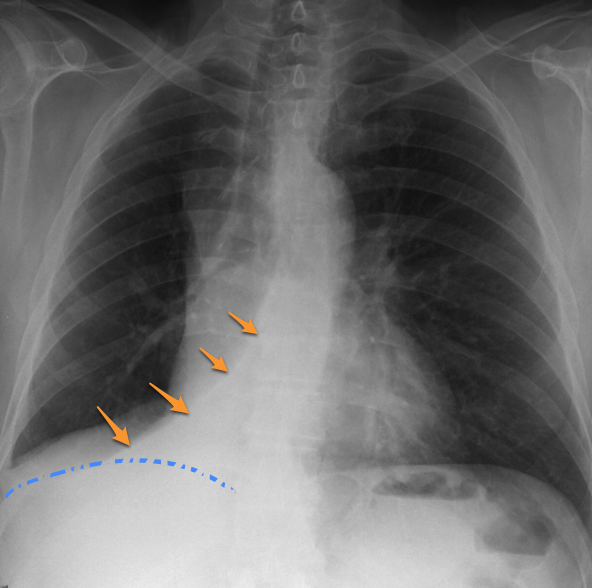

Left lower lobe atelectasis

The heart slightly rotates and the left hilum is pulled down. The flat waist sign describes the flattenin of the left heart border as a result of downward shift of hilar structures and resultant cardiac rotation.

Right lower lobe atelectasis

Mirror image of left lower lobe atelectasis. Collapsed lower lobe appears as a wedge-shaped retrocardiac opacity.